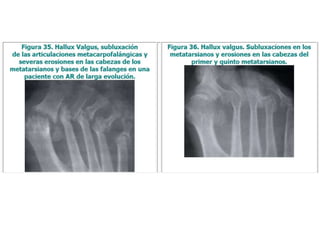

HALLAZGOS RADIOGRÁFICOS

RADIOGRAFÍAS

•Manos

•Pies

•Tórax

Evaluación

inicial:

• Inicialmente sin hallazgos tempranos

• 2 años de la enfermedad sin control:

– Erosión ósea y destrucción del cartílago

• Osteopenia periarticular

• Disminución del espacio articular por pérdida

de cartílago con erosión yuxtaarticular

• Finalmente erosiones quísticas óseas